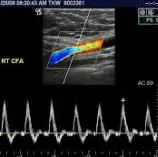

Периферен доплер

Периферниот доплер е неинвазивна дијагностичка процедура што се користи за проценка на протокот на крв во периферните артерии и вени, најчесто во екстремитетите. Оваа метода користи ултразвучни бранови за да се детектираат брзината и насоката на крвотокот, помагајќи во дијагностицирање на состојби како артериска стеноза, тромбоза, аневризми или венска инсуфициенција. Постапката е безболна, без зрачење и се изведува со нанесување гел на кожата и користење на доплер сонда. Резултатите се прикажуваат во форма на звучни сигнали или графички прикази, овозможувајќи прецизна анализа на васкуларните нарушувања. Периферниот доплер е клучен за рана дијагноза и следење на васкуларни болести, подобрувајќи го исходот на лекувањето.